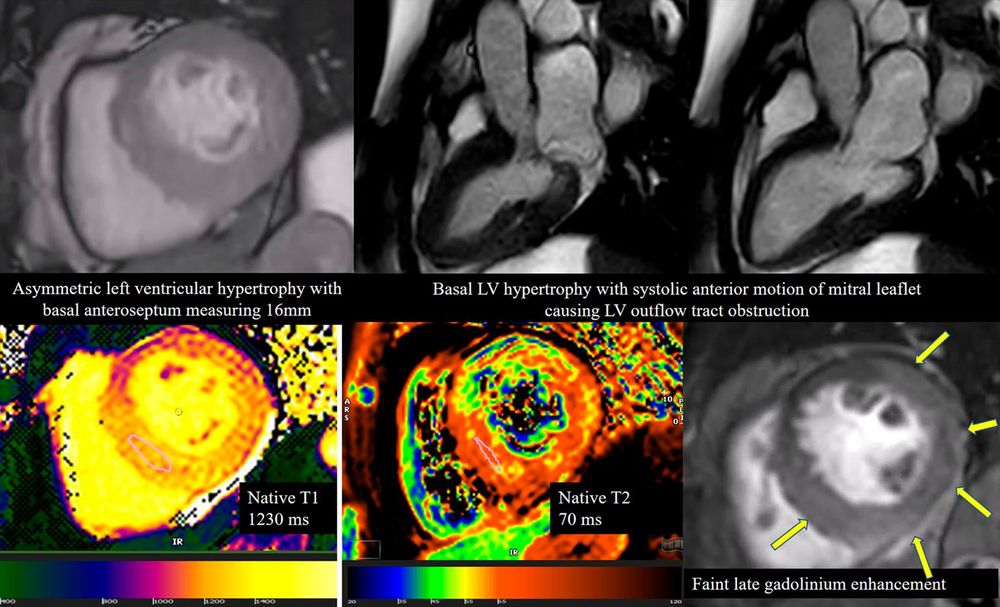

🫀 Pioneering: Discordant perfusion defects & #CAD in cardiac sarcoidosis—multimodality journey at #IJCVI!

🌐

Discordant myocardial perfusion defects and coronary artery disease – a multimodality imaging journey in the natural history of cardiac sarcoidosis

The International Journal of Cardiovascular Imaging - Cardiac sarcoidosis is a rare form of systemic sarcoidosis characterized by formation of non-caseating granulomas in the myocardium, leading to...

doi.org